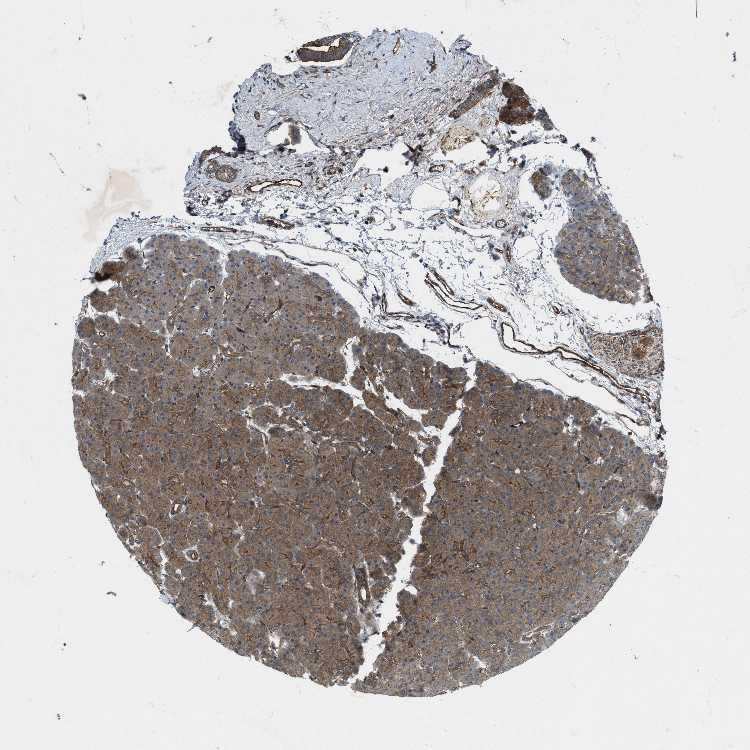

PANCREAS - Antibody stainingi

Antibody staining in the annotated cell types in the current human tissue is reported as not detected, low, medium, or high, based on conventional immunohistochemistry profiling in selected tissues. This score is based on the combination of the staining intensity and fraction of stained cells.

Each image is clickable and will lead to virtual microscopy that enables deeper exploration of all samples and also displays staining intensity scores, fraction scores and subcellular localization as well as patient and tissue information for each sample.

Antibody HPA019879Antibody HPA020134Antibody HPA029468

Exocrine glandular cells LowMediumMedium

Pancreatic endocrine cells Not detectedMediumMedium